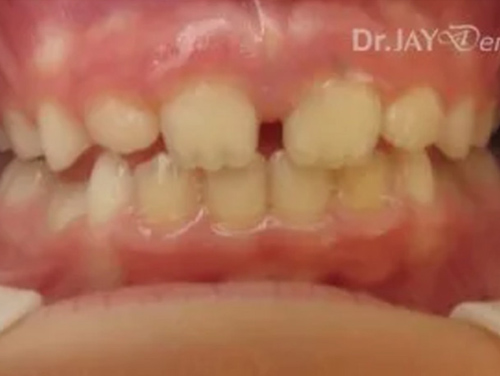

Patient had issue with spacing needed for erupting teeth , patient still going through treatment. After picture : in 6 months with Myofunctional therapy and tongue tie revision , jaws are widening and teeth are having space to erupt

Before

After